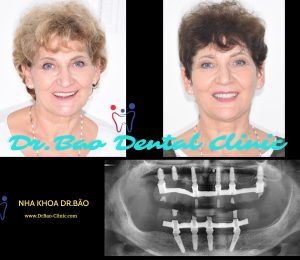

Mrs.Carrie visited our clinic to have consultation about her smile, she want to have total different new smile.

Tình trạng răng ban đầu

Thăm khám lần đầu tiên, bác sĩ nhận thấy hình dạng và màu sắc răng của cô Carrie không được thẩm mỹ:

- Răng hình tam giác, lộ nhiều lỗ đen giữa các răng.

- Màu sắc vàng, ố màu

- Kèm theo tình trạng mất răng sau hàm dưới

Kế hoạch đưa ra bao gồm:

- Trồng răng implant phục hồi răng mất phía sau

- Mặt dán sứ thẩm mỹ 10 răng cửa hàm trên cải thiện nụ cười

Kết quả sau khi trồng răng implant phía sau hàm dưới

Sau khi hoàn tất răng trên implant, chúng tôi bắt đầu bước sang giai đoạn thẩm mỹ răng phía trước hàm trên.

Thử răng tạm để chỉnh sửa màu sắc, hình dạng theo mong muốn của bệnh nhân và bác sĩ

Lắp răng sau cùng hàm trên – Form răng tự nhiên – màu sắc như thật